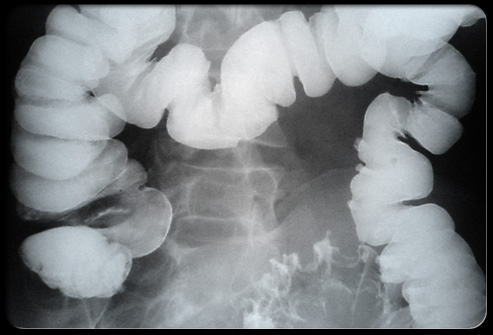

- ирригоскопия — рентгенологическое исследование с введением контрастного вещества в прямую кишку;